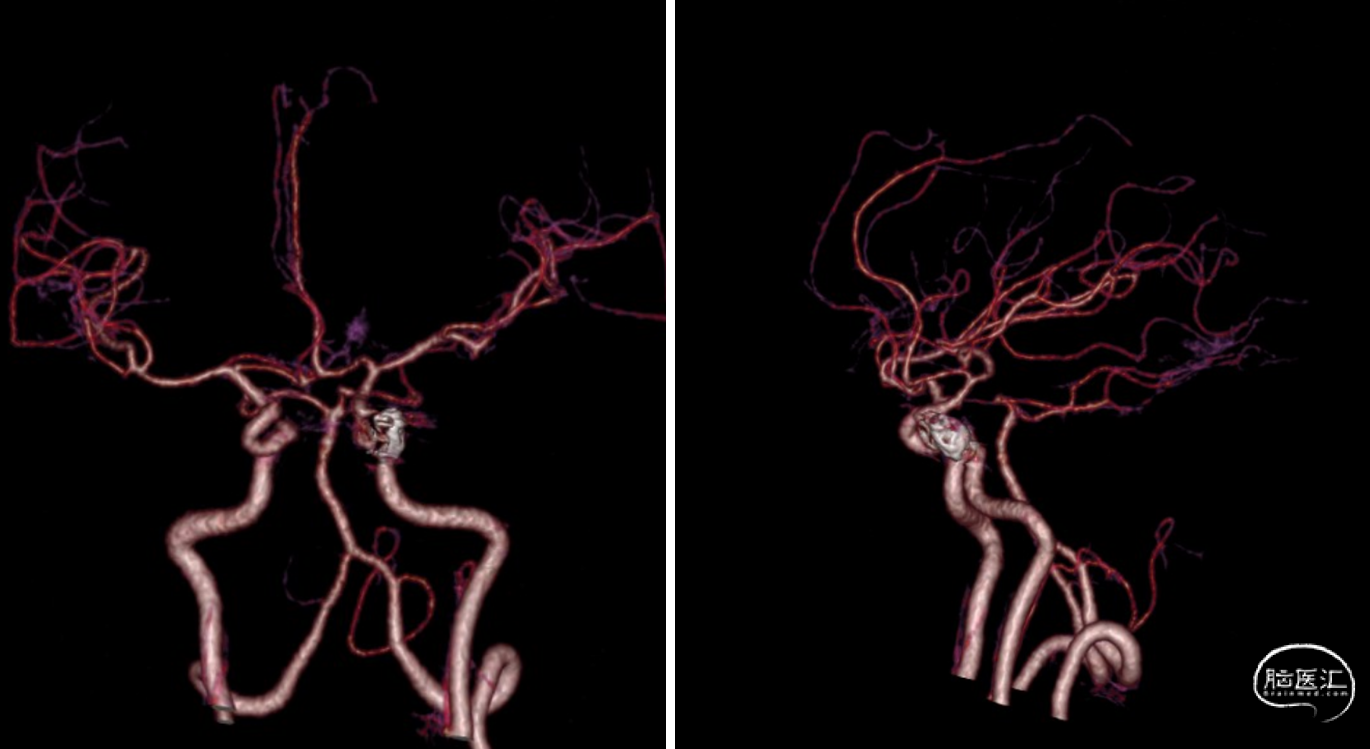

现病史:12小时前无明显诱因突发出现右侧肢体无力,伴言语不能,伴呕吐胃内容物3次,无人事不省,无肢体抽搐,无发热等。就诊当地医院,急查头颅CT示:“颅内出血”,予对症处理后转诊我院。我院急诊查头颅CTA示:“左侧基底节区及左侧额颞叶血肿伴大脑镰下疝、颞叶钩回疝及海马旁回疝可能,左侧颈内动脉C4段所见,考虑多发动脉瘤伴血管畸形,建议DSA检查”。

影像资料:CT、CTA

1.左侧基底节区及左侧额颞叶血肿 2.左侧颈内动脉C4段多发动脉瘤 3.左侧额颞叶血管动静脉畸形

DSA,“Ⅰ型主动脉弓”

术前诊断

修正诊断:

1. 左侧基底节区及左侧额颞叶血肿

2. 左侧颈内动脉C4段动脉瘤破裂致颈内动脉海绵窦瘘

3. 左侧额颞叶血管动静脉畸形?

最终诊断:

1. 左侧基底节区及左侧额颞叶血肿

2. 左侧颈内C4段动脉瘤破裂致颈内动脉海绵窦瘘(Barrow A型)

精确诊断:左侧颈内C4段动脉瘤破裂至大脑中浅静脉致左侧基底节区及左侧额颞叶静脉性梗死并出血转化。